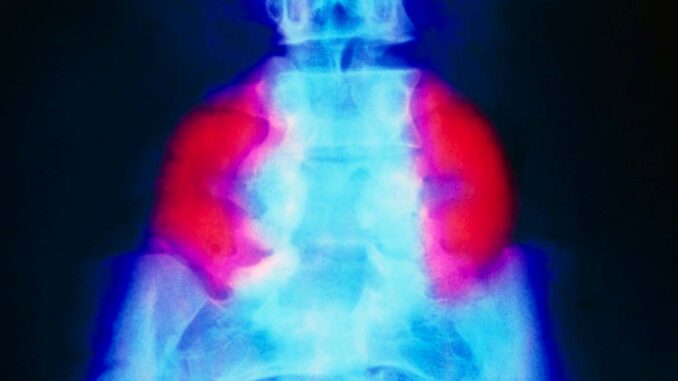

False color x-ray showing a large neural tube defect (red) on both sides of the lower back in someone with spina bifida

Spina bifida – which affects approx 1 in every 2,800 births in the US each year – occurs when the baby’s spine and spinal cord do not fully develop in the womb. In the most severe form of the disease, called myelomeningocele, the spinal cord and surrounding tissue protrude from the gap in the vertebrae, often impairing bowel and bladder motility and control. The cause of spina bifida is unknown, but folic acid deficiency during pregnancy increases the risk.